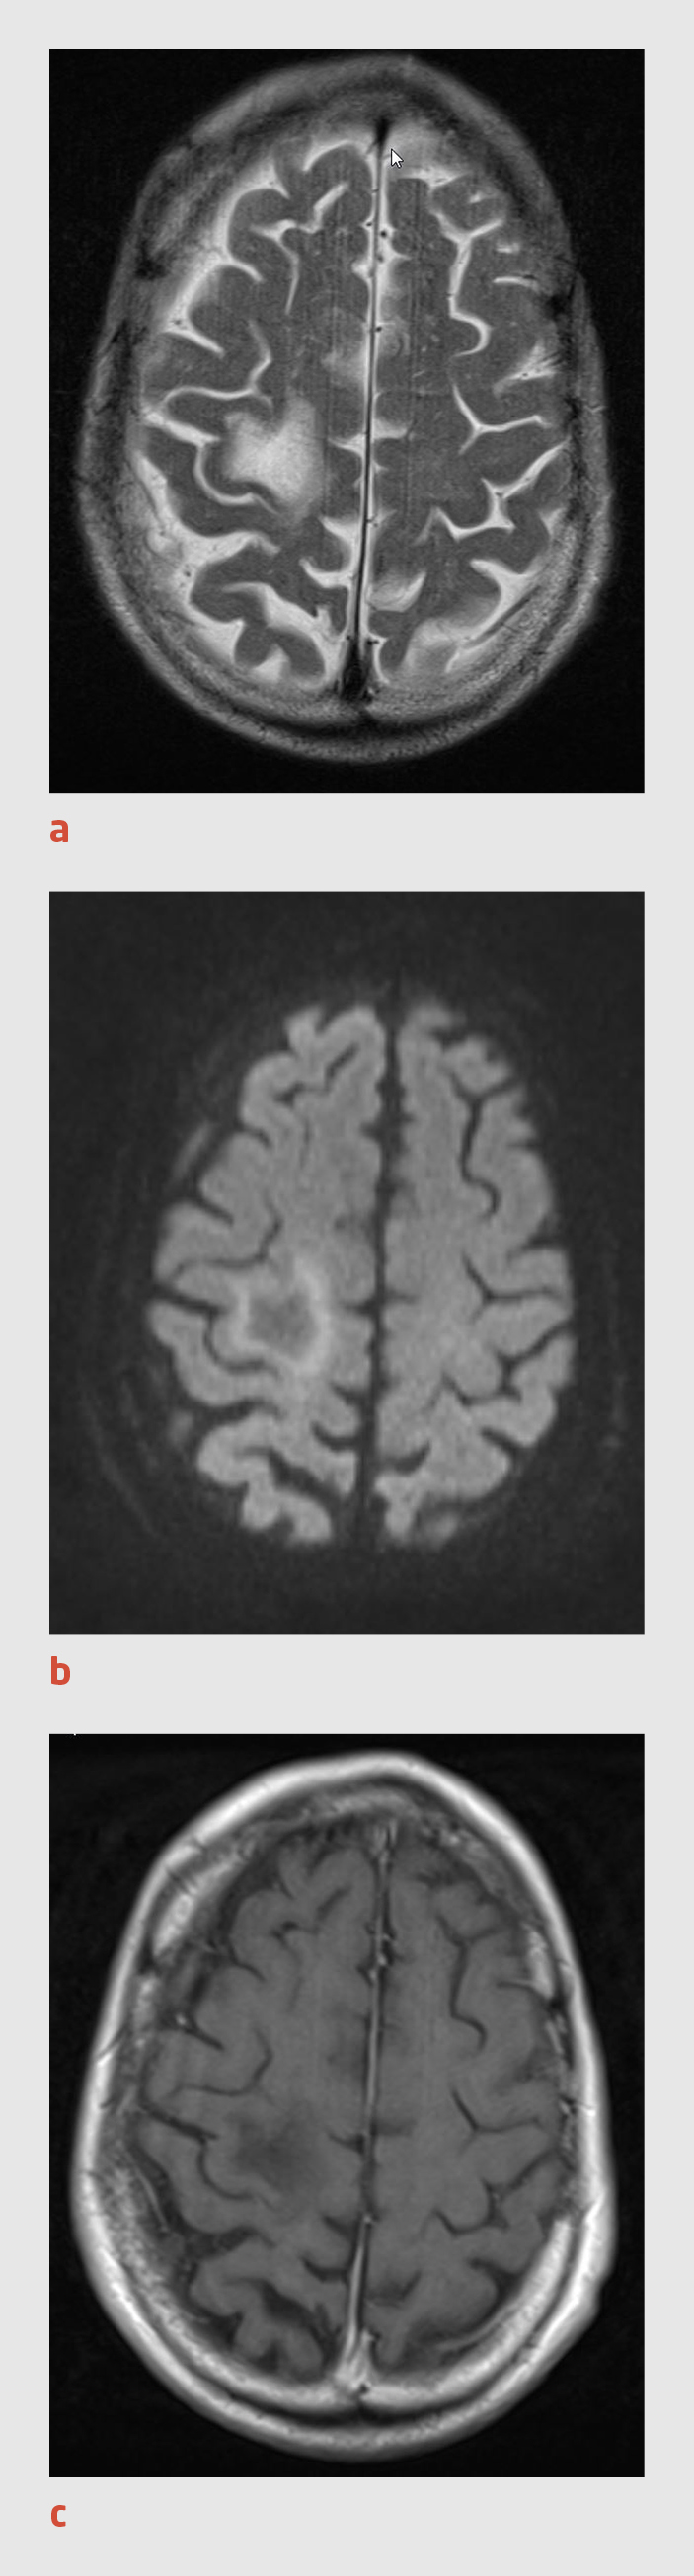

Patiënt, een 79-jarige man, kwam naar ons ziekenhuis vanwege verminderde kracht en coördinatie van zijn linker arm en been. Deze klachten waren in 1 week geleidelijk ontstaan. Patiënt had sinds 8 jaar een chronische lymfatische B-celleukemie (CLL), waarvoor hij reeds behandeld was met chloorambucil, rituximab, cyclofosfamide, vincristine en prednison. Een CT-scan van de hersenen liet hypodense afwijkingen zien in de rechter hemisfeer. Daarop stelden wij de diagnose ‘herseninfarct’ (figuur 1).

Figuur 1 |

CT-scan van de hersenen van een 79-jarige man met subacute neurologische uitvalsverschijnselen van de linker lichaamshelft. (a) Er is een hypodensiteit in de rechter hemisfeer te zien, waarbij alleen de witte stof is aangedaan. (b) Ook zijn er hypodensiteiten in beide hemisferen zichtbaar, welke goed kunnen passen bij vasculaire schade van oudere datum.

Bij patiënten met neurologische uitvalsverschijnselen zal meestal in eerste instantie een CT-scan van de hersenen verricht worden. Bij patiënten met PML kunnen op de scan een of meerdere hypodensiteiten in de witte stof zichtbaar zijn, waarbij de cortex vrijwel gespaard blijft. In retrospect waren zulke hypodensiteiten ook zichtbaar op de eerste CT-scan van onze patiënt (zie figuur 1a). Er waren echter ook afwijkingen te zien die goed bij ischemische schade kunnen passen (zie figuur 1b). Op een MRI-scan zijn de wittestofafwijkingen bij PML te zien als een hyperintens signaal op de T2-gewogen opname en de FLAIR-opname en als een hypo-intens signaal op de T1-gewogen opname. Deze afwijkingen hebben geen massawerking en kleuren normaliter niet aan na toediening van gadolinium (zie figuur 2). Geïsoleerde wittestofafwijkingen op een CT- of MRI-scan maken cerebrale ischemie onwaarschijnlijker. Omdat de afwijkingen niet aankleuren na toediening van contrast, is een maligniteit eveneens onwaarschijnlijk.